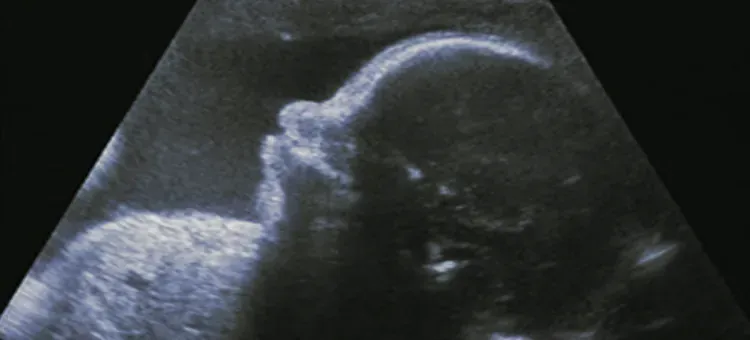

W 27. tygodniu ciąży Twoje dziecko robi naprawdę imponujące postępy. Jego waga wynosi już średnio od 900 g do około 1000 g, czyli blisko kilograma! Jeśli chodzi o długość, maluch mierzy około 35-37 cm od głowy do stóp. W pozycji skulonej, czyli tzw. długość ciemieniowo-siedzeniowa, to około 24-25 cm. Aby lepiej sobie to wyobrazić, często porównujemy jego rozmiar do dużego kalafiora, brokuła, cukinii, a wagę do paczki mąki. To naprawdę spory postęp od maleńkiej fasolki, prawda?

W 27. tygodniu ciąży Twoje dziecko wciąż ma sporo miejsca na akrobacje w Twoim brzuchu i może swobodnie zmieniać pozycje. Jednak powoli, ale sukcesywnie, przygotowuje się do ułożenia główkowego, które jest najbardziej optymalne do porodu. Zazwyczaj pozycja ta stabilizuje się dopiero po 32. tygodniu ciąży, więc na razie maluch może być ułożony miednicowo, poprzecznie, a nawet zmieniać ułożenie kilka razy dziennie. Nie ma powodu do niepokoju, jeśli jeszcze nie jest główką w dół ma na to jeszcze trochę czasu.